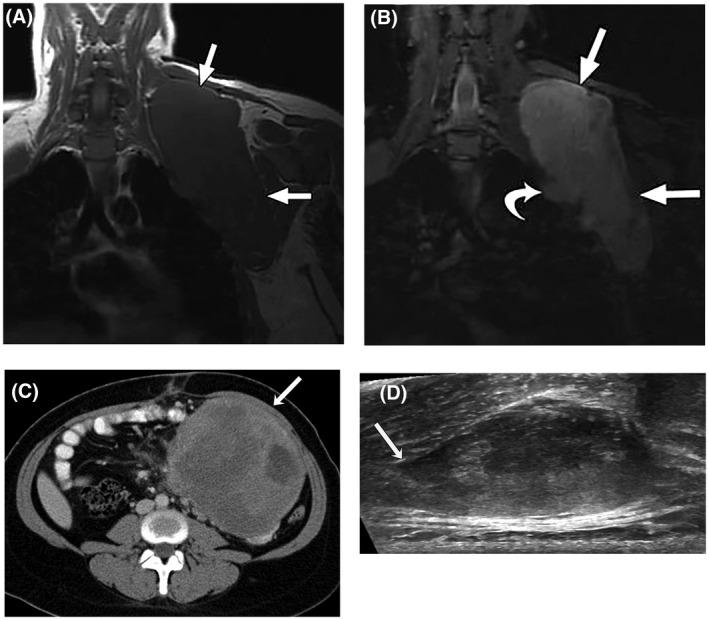

Desmoid tumors (DTs) are rare soft tissue mesenchymal neoplasms that may be associated with impairments, disfigurement, morbidity, and (rarely) mortality. DT disease course can be unpredictable. Most DTs are sporadic, harboring somatic mutations in the gene that encodes for β-catenin, whereas DTs occurring in patients with familial adenomatous polyposis have germline mutations in the APC gene, which encodes for a protein regulator of β-catenin. Pathology review by an expert soft tissue pathologist is critical in making a diagnosis. Magnetic resonance imaging is preferred for most anatomic locations. Surgery, once the standard of care for initial treatment of DT, is associated with a significant risk of recurrence as well as avoidable morbidity because spontaneous regressions are known to occur without treatment. Consequently, active surveillance in conjunction with pain management is now recommended for most patients. Systemic medical treatment of DT has evolved beyond the use of hormone therapy, which is no longer routinely recommended. Current options for medical management include tyrosine kinase inhibitors as well as more conventional cytotoxic chemotherapy (e.g., anthracycline-based or methotrexate-based regimens). A newer class of agents, γ-secretase inhibitors, appears promising, including in patients who fail other therapies, but confirmation in Phase 3 trials is needed. In summary, DTs present challenges to physicians in diagnosis and prognosis, as well as in determining treatment initiation, type, duration, and sequence. Accordingly, evaluation by a multidisciplinary team with expertise in DT and patient-tailored management are essential. As management strategies continue to evolve, further studies will help clarify these issues and optimize outcomes for patients.

硬纤维瘤(DTs)是一种罕见的软组织间叶性肿瘤,可能导致功能障碍、畸形、发病率(罕见情况下导致死亡率)升高。DT 的病程可能不可预测。大多数 DTs 是散发性的,存在编码β-连环蛋白的基因突变,而发生于家族性腺瘤性息肉病患者的 DTs 则存在 APC 基因突变,该基因编码β-连环蛋白的蛋白调节因子。由软组织病理专家进行病理审查对于做出诊断至关重要。磁共振成像(MRI)是大多数解剖部位的首选检查方法。手术曾是 DT 初始治疗的标准治疗方法,但与高复发风险和可避免的发病率相关,因为已知 DT 会自发消退而无需治疗。因此,目前建议大多数患者进行积极监测并结合疼痛管理。DT 的系统治疗已超出激素治疗的范围,目前不再常规推荐。目前用于医学治疗的选择包括酪氨酸激酶抑制剂以及更传统的细胞毒性化疗(例如,基于蒽环类药物或甲氨蝶呤的方案)。一类新型药物γ-分泌酶抑制剂似乎很有前景,包括在其他治疗失败的患者中,但仍需要 III 期临床试验的证实。总之,DT 给医生在诊断和预后方面以及在确定治疗的起始、类型、持续时间和顺序方面带来了挑战。因此,需要由在 DTs 方面具有专业知识的多学科团队进行评估并制定个体化的管理方案。随着管理策略的不断发展,进一步的研究将有助于阐明这些问题并优化患者的结局。